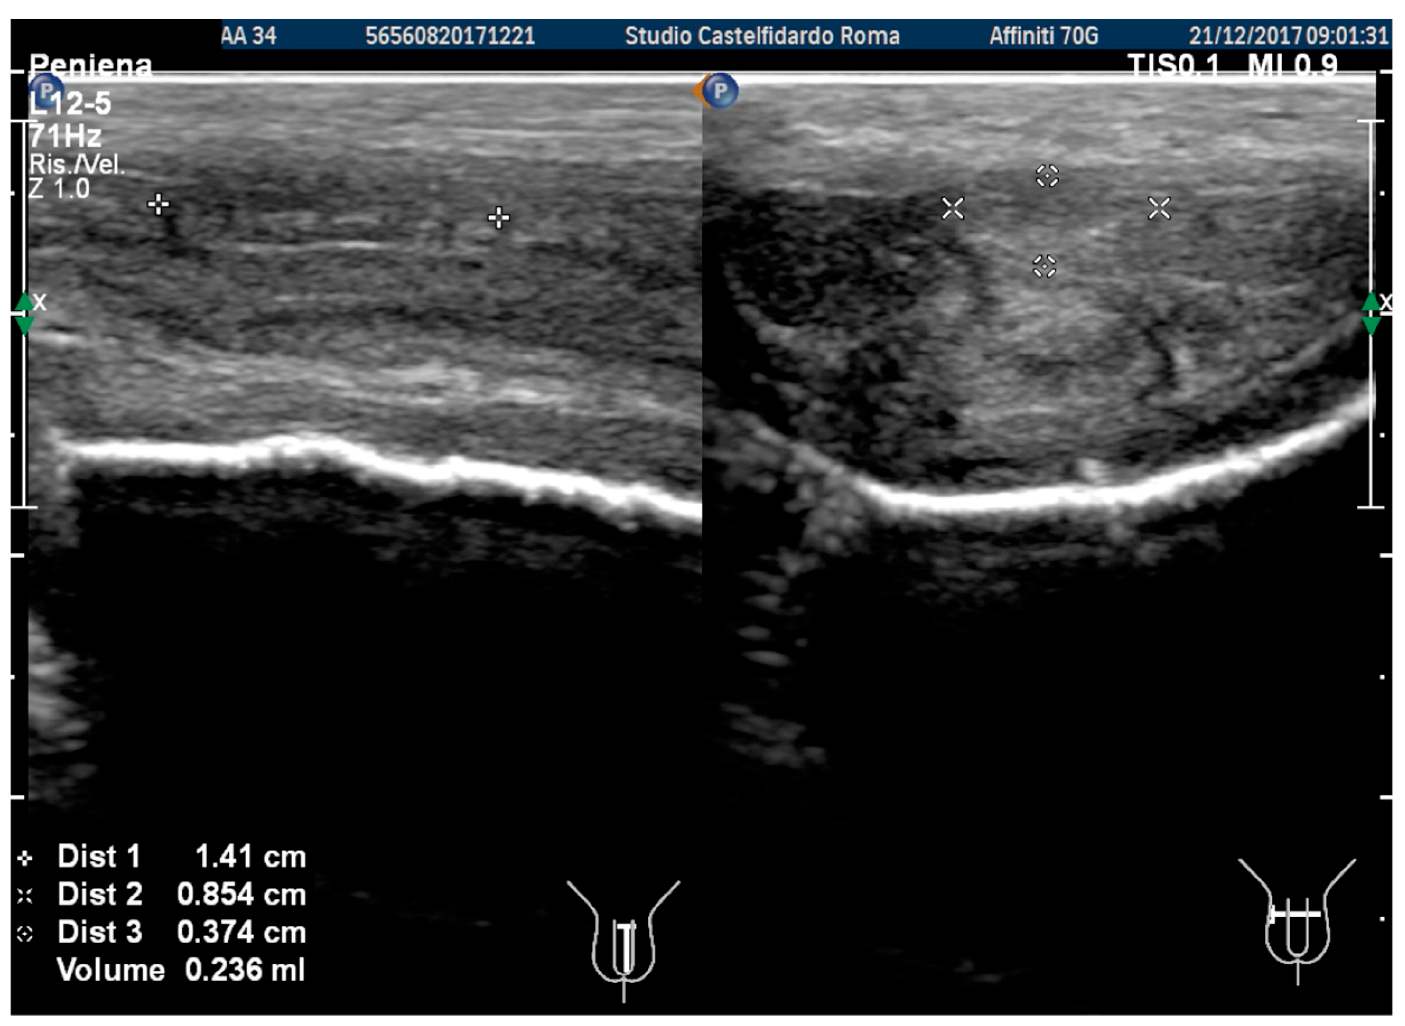

| 3 | 33 years | None | Middle third | (A) 20.6 × 15.2 × 4.42 mm volume = 724 mm3 + some small calcifications, the largest of which measured 1.9 × 4.1 mm | (A) 30-degree dorsal penile curvature | (A) score 2 | (A) score 26 | 3 years and 5 months | orally: Silymarin 400 mg + Ginkgo biloba 250 mg + Propolis 600 mg + Bilberry 160 mg + Vitamin E 800 IU/once a day, for 41 months. + topically: Propolis creme/twice a day/for 41 months. + peri-plaque penile injections: Pentoxifylline 100 mg (30 G needle) every 15 days for 6 months, and then monthly for 12 months, and then 1 injection every other month. for 12 months (total = 30 injections) |

| (B) No plaque detected | (B) None | (B) score 0 (after six months) | (B) score 27 |